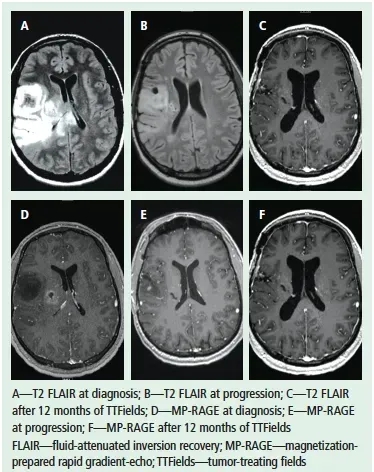

《临床肿瘤护理杂志(CJON)》曾记录一则经典病例:一名28岁男性因癫痫发作、意识恢复迟缓就医,MRI检查显示右侧颞叶与顶叶交界处存在病变。经高剂量类固醇联合左乙拉西坦(Keppra®)稳定病情后,患者接受开颅肿瘤切除术,术后病理确诊为胶质母细胞瘤。

术后,患者先完成放疗联合替莫唑胺化疗的初始治疗,间隔1个月后,继续接受为期1年的替莫唑胺(TMZ)辅助化疗。6年后,患者因右手间歇性颤抖复查,MRI显示原肿瘤区域出现2.2cm×1.5cm大小的强化病灶;二次手术后病理证实为复发性胶质母细胞瘤,且伴随放射后改变。

神经肿瘤科团队对多种方案(含临床试验选项)评估后,患者最终选择肿瘤电场疗法(TTFields)。令人振奋的是,经过7个月治疗,患者恢复状况良好。下图展示了该患者在电场疗法治疗前后的MRI对比。

▲图源“MDPI”,版权归原作者所有,如无意中侵犯了知识产权,请联系我们删除